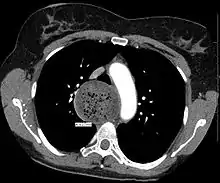

![]() | |

A chest X-ray showing achalasia (arrows point to the outline of the massively dilated esophagus) | |